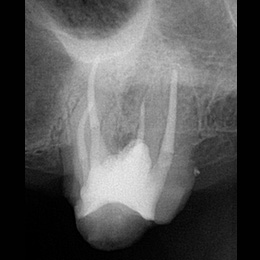

Fallbeispiel: Zahn 14 mit 3 Kanälen

Unbehandelte Wurzelkanäle – eine der häufigsten Ursachen für persistierende Infektionen nach einer Wurzelkanalbehandlung. Mit einer Revisionsbehandlung können unbehandelte Kanäle behandelt und der Zahn erhalten werden.